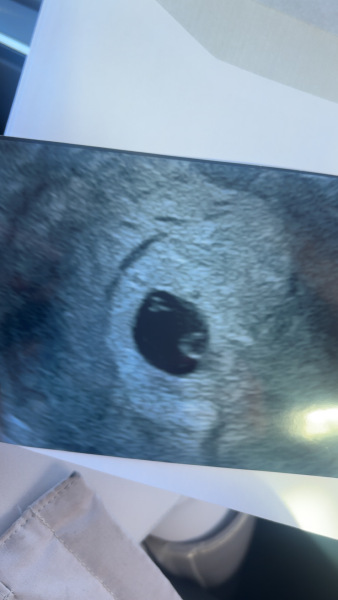

Scan 5 weeks 4 days

Hi everyone I got a scan today and I’m wondering what others twin pregnancies looked like and what you guys think?

I could see one of them saying is there two, but they were reluctant to say with me being so early on so I’m booked in for another scan on the 4th of December so I will know then 😊

Certainly looks like two!